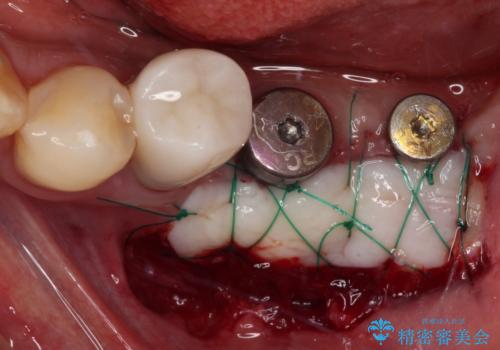

インプラント埋入後、手前のインプラント周りの丈夫な歯肉(角化歯肉)が失われてしまったため、角化歯肉の移植を行うこととなりました。

十分な角化歯肉が獲得でき、清掃性の高い環境が達成されました。